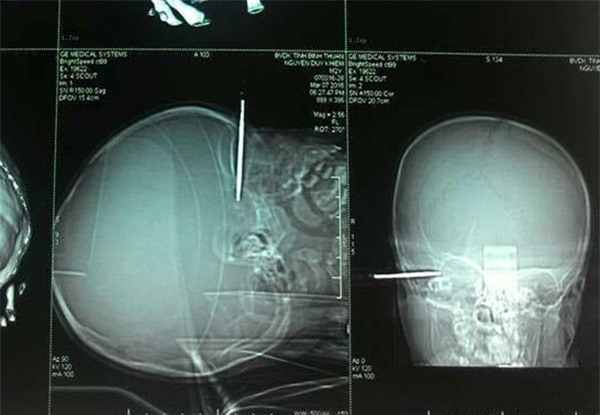

Bé 14 tháng tuổi bị tuốc nơ vít đâm thủng thái dương

Ngày 9/3, Bệnh viện đa khoa Bình Thuận cho biết, sau 2 ngày phẫu thuật, sức khỏe bé trai Nguyễn Duy Khiêm (14 tháng tuổi, phường Mũi Né, TP Phan Thiết, Bình Thuận) dần hồi phục, tỉnh táo, có thể ăn uống. Bệnh nhi đang được các bác sĩ theo dõi, tiếp tục điều trị.

Trước đó, ngày 7/3, Khiêm nhặt được chiếc tuốc nơ vít trong nhà cầm chơi. Bé chập chững bước đi sau đó vấp ngã và bị vật nhọn đâm vào đầu.

Phát hiện vụ việc, người thân đưa bé đến bệnh viện cấp cứu trong tình trạng nguy kịch. Các bác sĩ thực hiện xét nghiệm, chụp phim và tổ chức mổ cấp cứu ngay sau đó. May mắn, chiếc tuốc nơ vít cắm vào thái dương bệnh nhi nhưng chưa gây tổn thương não.